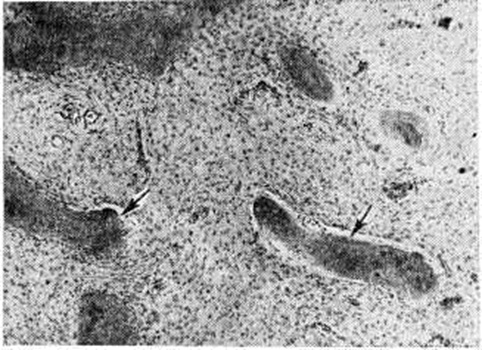

Фиброзная остеодисплазияФиброзная остеодисплазия (osteodysplasia fibrosa; синонимы: фиброзная дисплазия костей, болезнь Лихтенстайна — Брайцева, дисплазия Яффе — Лихтенстайна) — порок развития костной системы, в основе которого лежит нарушение окостенения, приводящее к деформации костей. Впервые выделена в самостоятельную нозологическую форму в 1938 год американский учёным Л. Лихтенстайном под названием полиостотическая фиброзная дисплазия. В настоящий, время большинством исследователей признано, что Фиброзная остеодисплазия вязана с нарушением нормального окостенения скелета в период эмбрионального развития. По мнению Т. П. Виноградовой (1960), Фиброзная остеодисплазия относится к группе процессов, пограничных с доброкачественными опухолями. Способность рецидивировать после удаления и подвергаться малигнизации подтверждает эту точку зрения и позволяет рассматривать Фиброзная остеодисплазия как предопухолевое состояние. По данным М. В. Волкова (1974), среди новообразований и дисплазий скелета, наблюдаемых в детском возрасте, Фиброзная остеодисплазия составляет 8,5%. В соответствии с числом вовлечённых в патологический процесс костей различают монооссальную и полиоссальную формы Фиброзная остеодисплазия Патологический изменения чаще возникают и в большей степени проявляются в челюстях (смотри полный свод знаний: Фиброзная остеодисплазия челюстей), в проксимальных отделах конечностей. Нижние конечности поражаются чаще, чем верхние. Из плоских костей при Фиброзная остеодисплазия страдают преимущественно передние отделы свода черепа и подвздошные кости. В длинных трубчатых костях процесс, как правило, локализуется в метафизах, откуда распространяется на диафиз. Зона эпифизарного хряща является своеобразным барьером для Фиброзная остеодисплазия В редких случаях эпифизы поражаются первично, чаще же в них находят вторичные неспецифические изменения — остеопороз и деформацию. Патологическая анатомия. Характер патологоанатомических изменений при Фиброзная остеодисплазия не зависит от формы заболевания. Поражённые отделы костей деформированы, утолщены, длинные трубчатые кости нередко изогнуты. На распиле костей обнаруживают различной величины и формы очаги белёсой плотной ткани, обычно содержащей мелкие костные включения. В ряде случаев происходит почти полное замещение кости этой тканью. Над очагами Фиброзная остеодисплазия пластинка компактного (коркового) вещества истончена, на отдельных участках прерывается; в толще патологический ткани располагаются кисты, содержащие прозрачную жидкость. При микроскопическом исследовании поражённых отделов костей обнаруживается волокнистая соединительная ткань, представленная коллагеновыми, ретикулиновыми волокнами и фибробластоподобными клетками, среди которых располагаются примитивные костные балки, распределяющиеся бессистемно (рисунок 1). Нередко периферические отделы костных балок состоят из остеоидной ткани, реже балки целиком состоят из этой ткани. Иногда формирующиеся костные структуры крайне примитивны и имеют вид более или менее обособленных сгущений коллагеновых волокон без отложения в них солей кальция. Эти структуры рассматривают как предстадию образования костных балок. У разных больных и в различных очагах Фиброзная остеодисплазия одного и того же больного и даже в разных участках одного очага гистологический картина может быть неодинаковой. Она различается по характеру костных структур, количественному соотношению этих структур с волокнистой тканью, морфологии клеток и плотности расположения волокон. У некоторых больных в патологический очагах или их участках развивается более или менее густая сеть костных балок, иногда напоминающая губчатую остеому (смотри полный свод знаний). Среди волокон соединительной ткани встречаются скопления остеокластов; изредка обнаруживаются участки типа остеобластокластомы (смотри полный свод знаний), иногда выявляются скопления ксантомных клеток (смотри полный свод знаний: Ксантома). Клиническая картина разнообразна и зависит от формы Фиброзная остеодисплазия, локализации процесса и распространённости костных поражений. Больные жалуются на боли при ходьбе, интенсивность которых усиливается при прогрессировании патологический процесса. Нередко первым признаком заболевания являются повторяющиеся патологический переломы. Наиболее частый признак Фиброзная остеодисплазия— деформация кости от едва заметного её искривления до значительного изгиба целого сегмента конечности. |